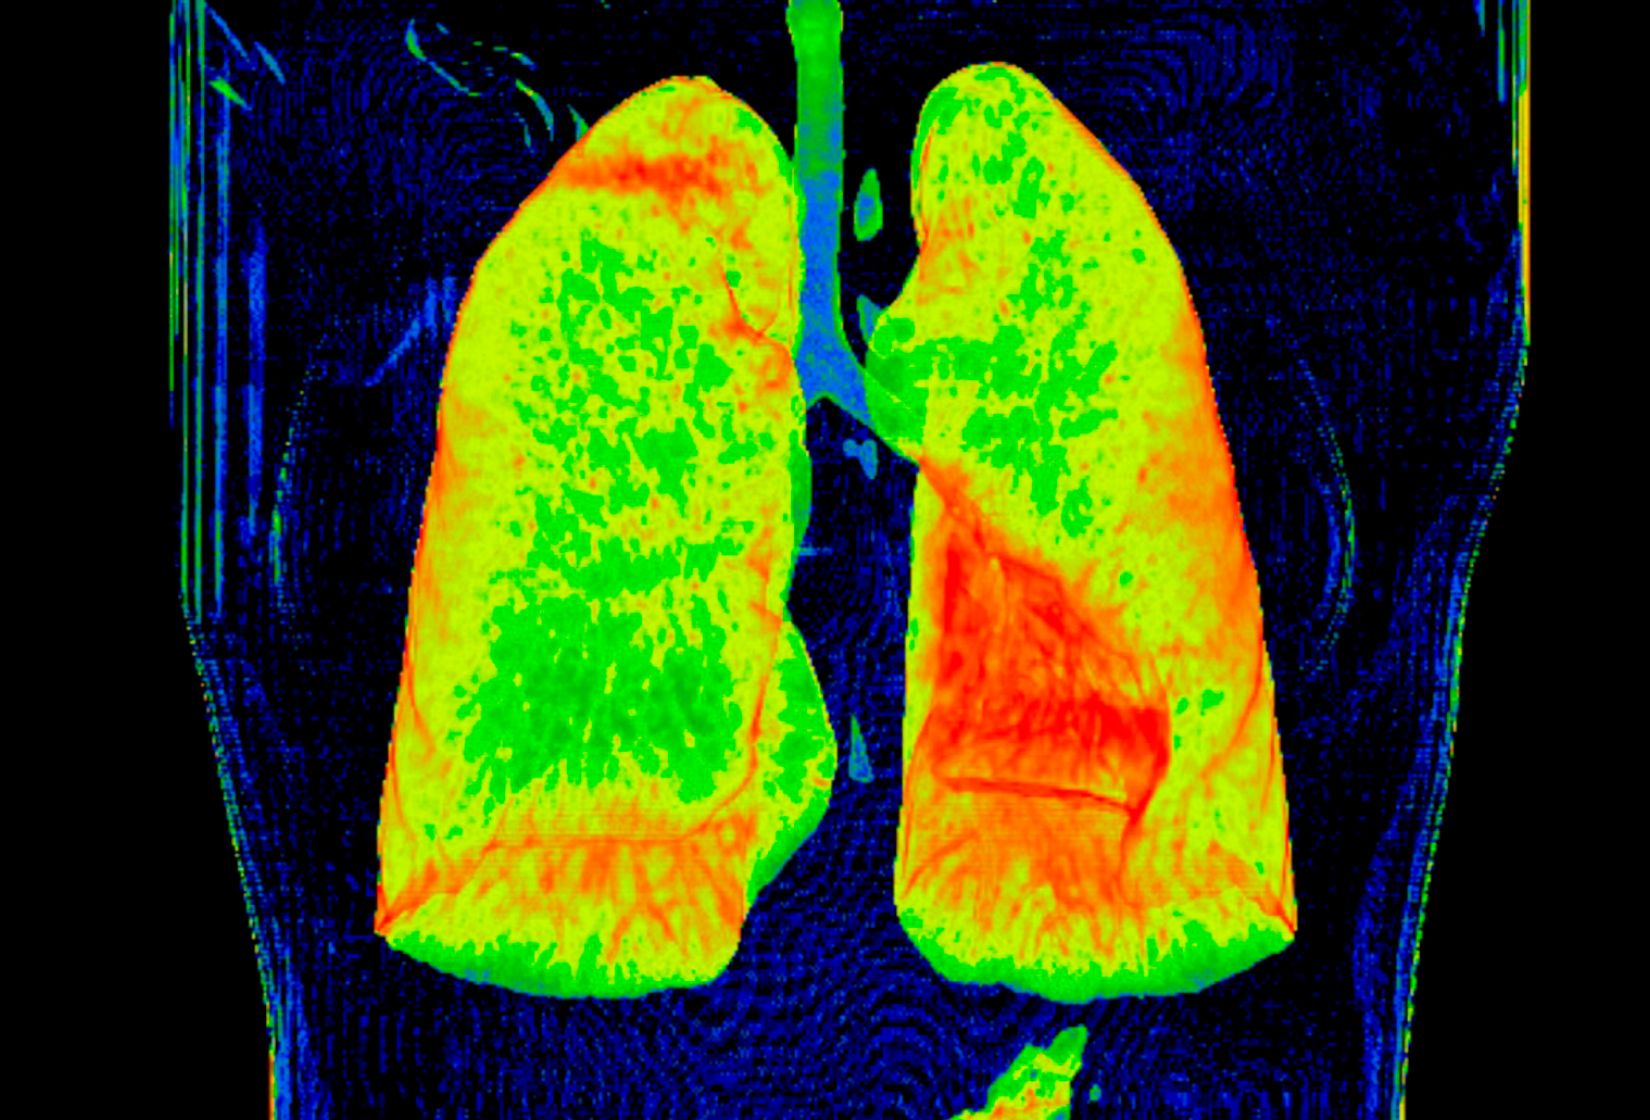

Durch sehr schnelle Spannungswechsel an der CT-Röntgenröhre ist auch eine sogenannte spektrale Bildgebung möglich. Diese ermöglicht, Gewebe besser zu charakterisieren oder auch Kontrastmittel zu sparen (z.B. bei eingeschränkter Nierenfunktion). Bei einem Verschluss der Lungenarterien kann so zum Beispiel das minderversorgte Gewebe dargestellt werden. Man gewinnt u.a. zusätzliche wertvolle Informationen zum Schweregrad der Erkrankung.